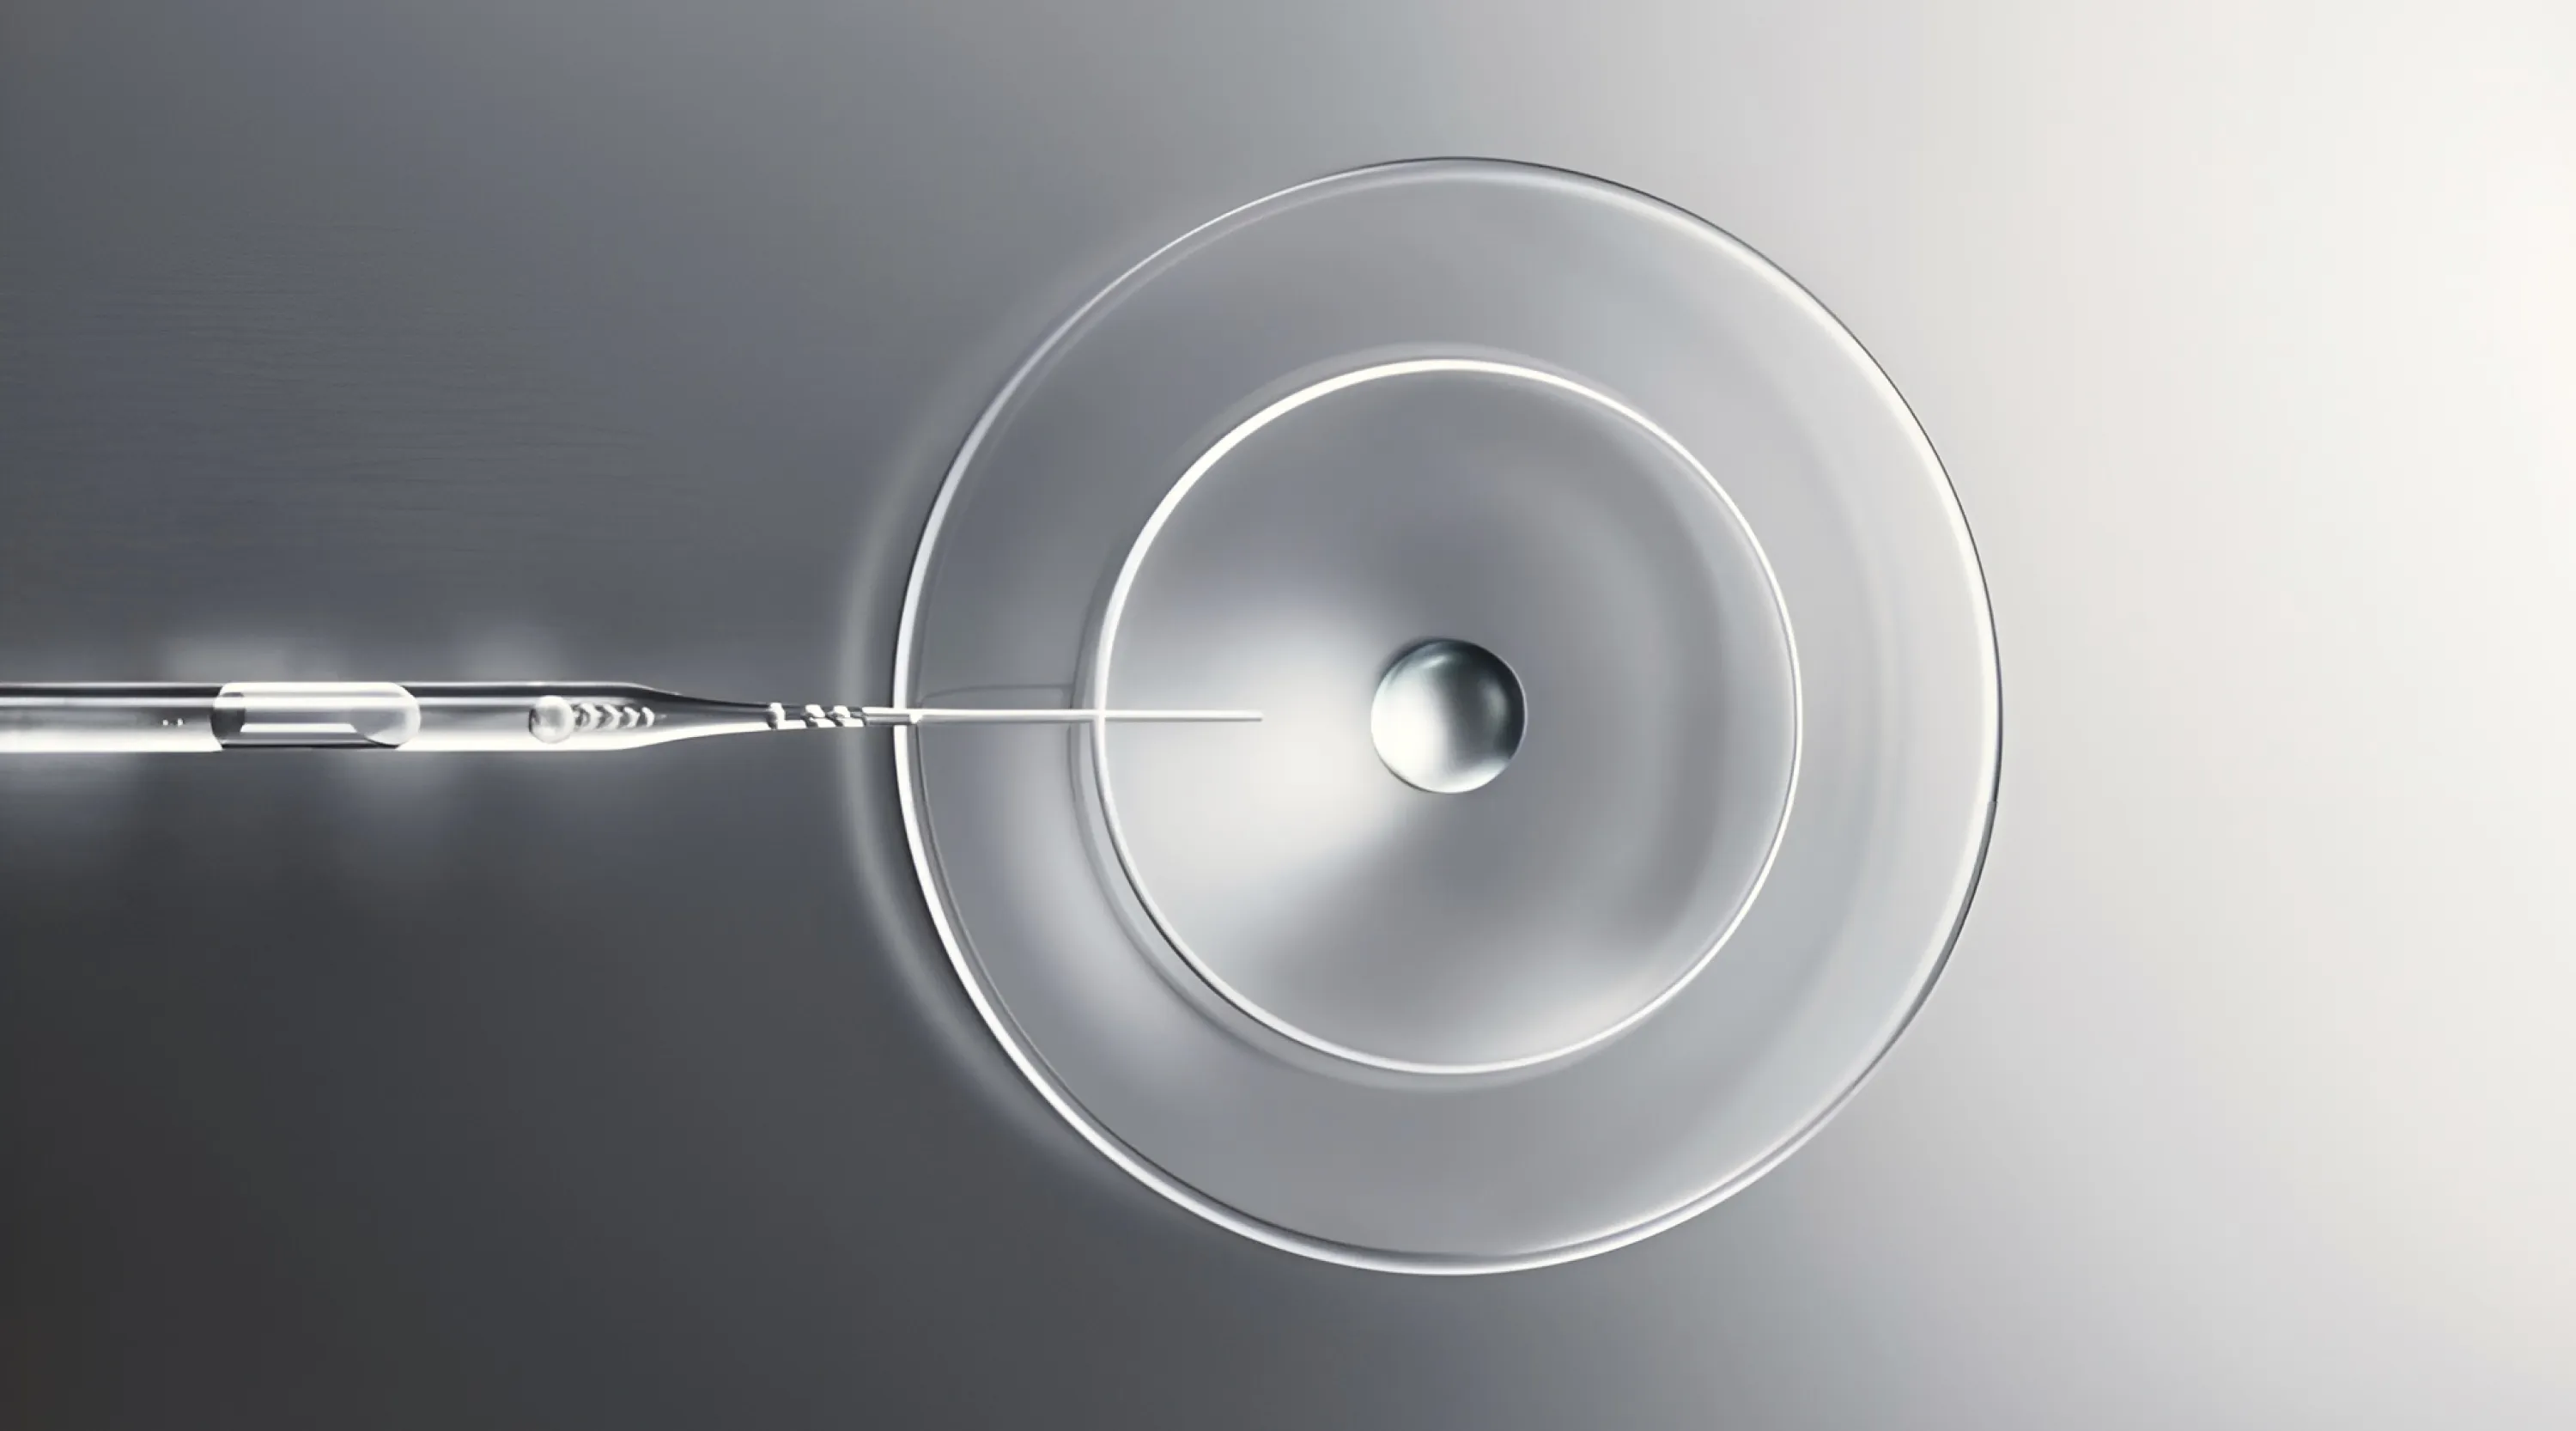

▪️ Регенеративная терапия в коррекции постакне. Как подобрать нужную концентрацию PRP?

▪️ Обоснование применения Ycellbio в дерматологии.